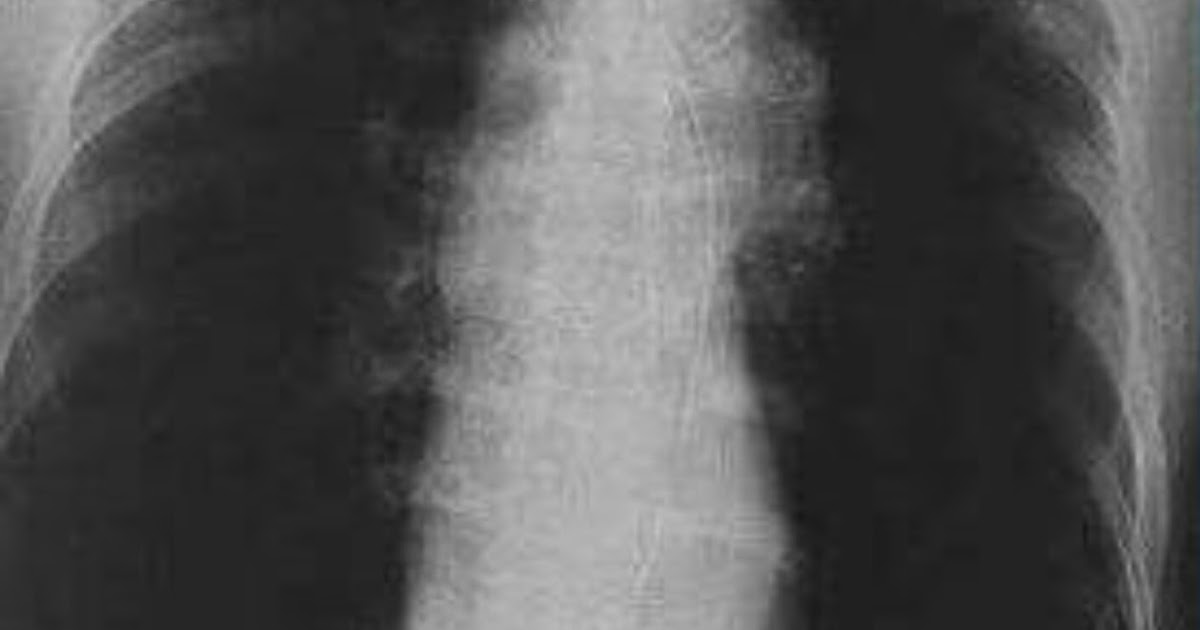

DrRadio EMPHYSEMA Chest xray PA view Does A Chest Xray Show Emphysema Ct scan a ct scan may show the type of copd like emphysema or. — except in the case of very advanced disease with bulla formation, chest radiography does not image emphysema. This may be partly because of the heart changing how it sits in the chest to make room for the. — if your healthcare provider suspects. Does A Chest Xray Show Emphysema.

Emphysema lung disease, frontal chest Xray Stock Image C048/6078 Does A Chest Xray Show Emphysema Ct scan a ct scan may show the type of copd like emphysema or. — except in the case of very advanced disease with bulla formation, chest radiography does not image emphysema. This may be partly because of the heart changing how it sits in the chest to make room for the. — if your healthcare provider suspects. Does A Chest Xray Show Emphysema.